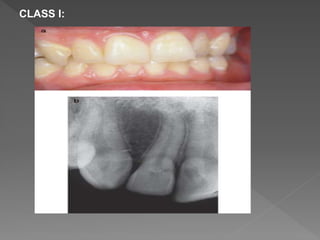

CLASS I:

• #50 Class 1 – Denotes a small invasive resorptive lesion near the cervical area with shallow penetration into dentine. Class 2 – Denotes a well-defined invasive resorptive lesion that has penetrated close to the coronal pulp chamber but shows little or no extension into the radicular dentine. Class 3 – Denotes a deeper invasion of dentine by resorbing tissue, not only involving the coronal dentine but also extending into the coronal third of the root. Class 4 – Denotes a large invasive resorptive process that has extended beyond the coronal third of the root.